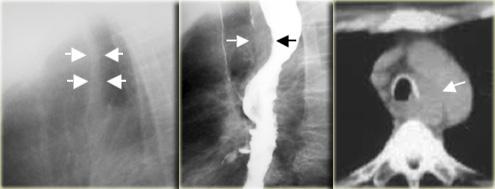

Bên trái là hình ảnh một bệnh nhân bị tụ máu thực quản.

Bệnh nhân nhập viện với triệu chứng đau ngực và khó nuốt sau khi nôn mửa.

Ngoài hình ảnh động mạch chủ ngoằn ngoèo, X-quang ngực bình thường.

Chụp thực quản barium cho thấy lòng thực quản hẹp (các mũi tên) trên phim thẳng và lòng thực quản dẹt trên phim nghiêng (các đầu mũi tên), gợi ý tụ máu trong thành thực quản.

Trên CT, chẩn đoán tụ máu trong thành thực quản được xác nhận.

Khối tụ máu thành thực quản tăng tỷ trọng (đầu mũi tên) được thấy cạnh ống thông mũi – dạ dày (mũi tên).

Bên trái là hình ảnh một bệnh nhân có biến chứng sau nội soi phức tạp.

Can thiệp dụng cụ gây rách niêm mạc và tụ máu trong thành thực quản dạng bóc tách, tạo ra hình ảnh lòng đôi với dải niêm mạc phân tách (các mũi tên).

Ngoài cùng bên trái là hình ảnh thoát thuốc cản quang trong thành thực quản (mũi tên) sau nong đoạn xa điều trị co thắt tâm vị.

Ở giữa là hình ảnh thoát thuốc cản quang trong thành thực quản (mũi tên) sau nội soi phức tạp.

Bên phải là hình ảnh thủng thực quản sau sinh thiết với thuốc cản quang thoát ra ngoài lòng thực quản (mũi tên).